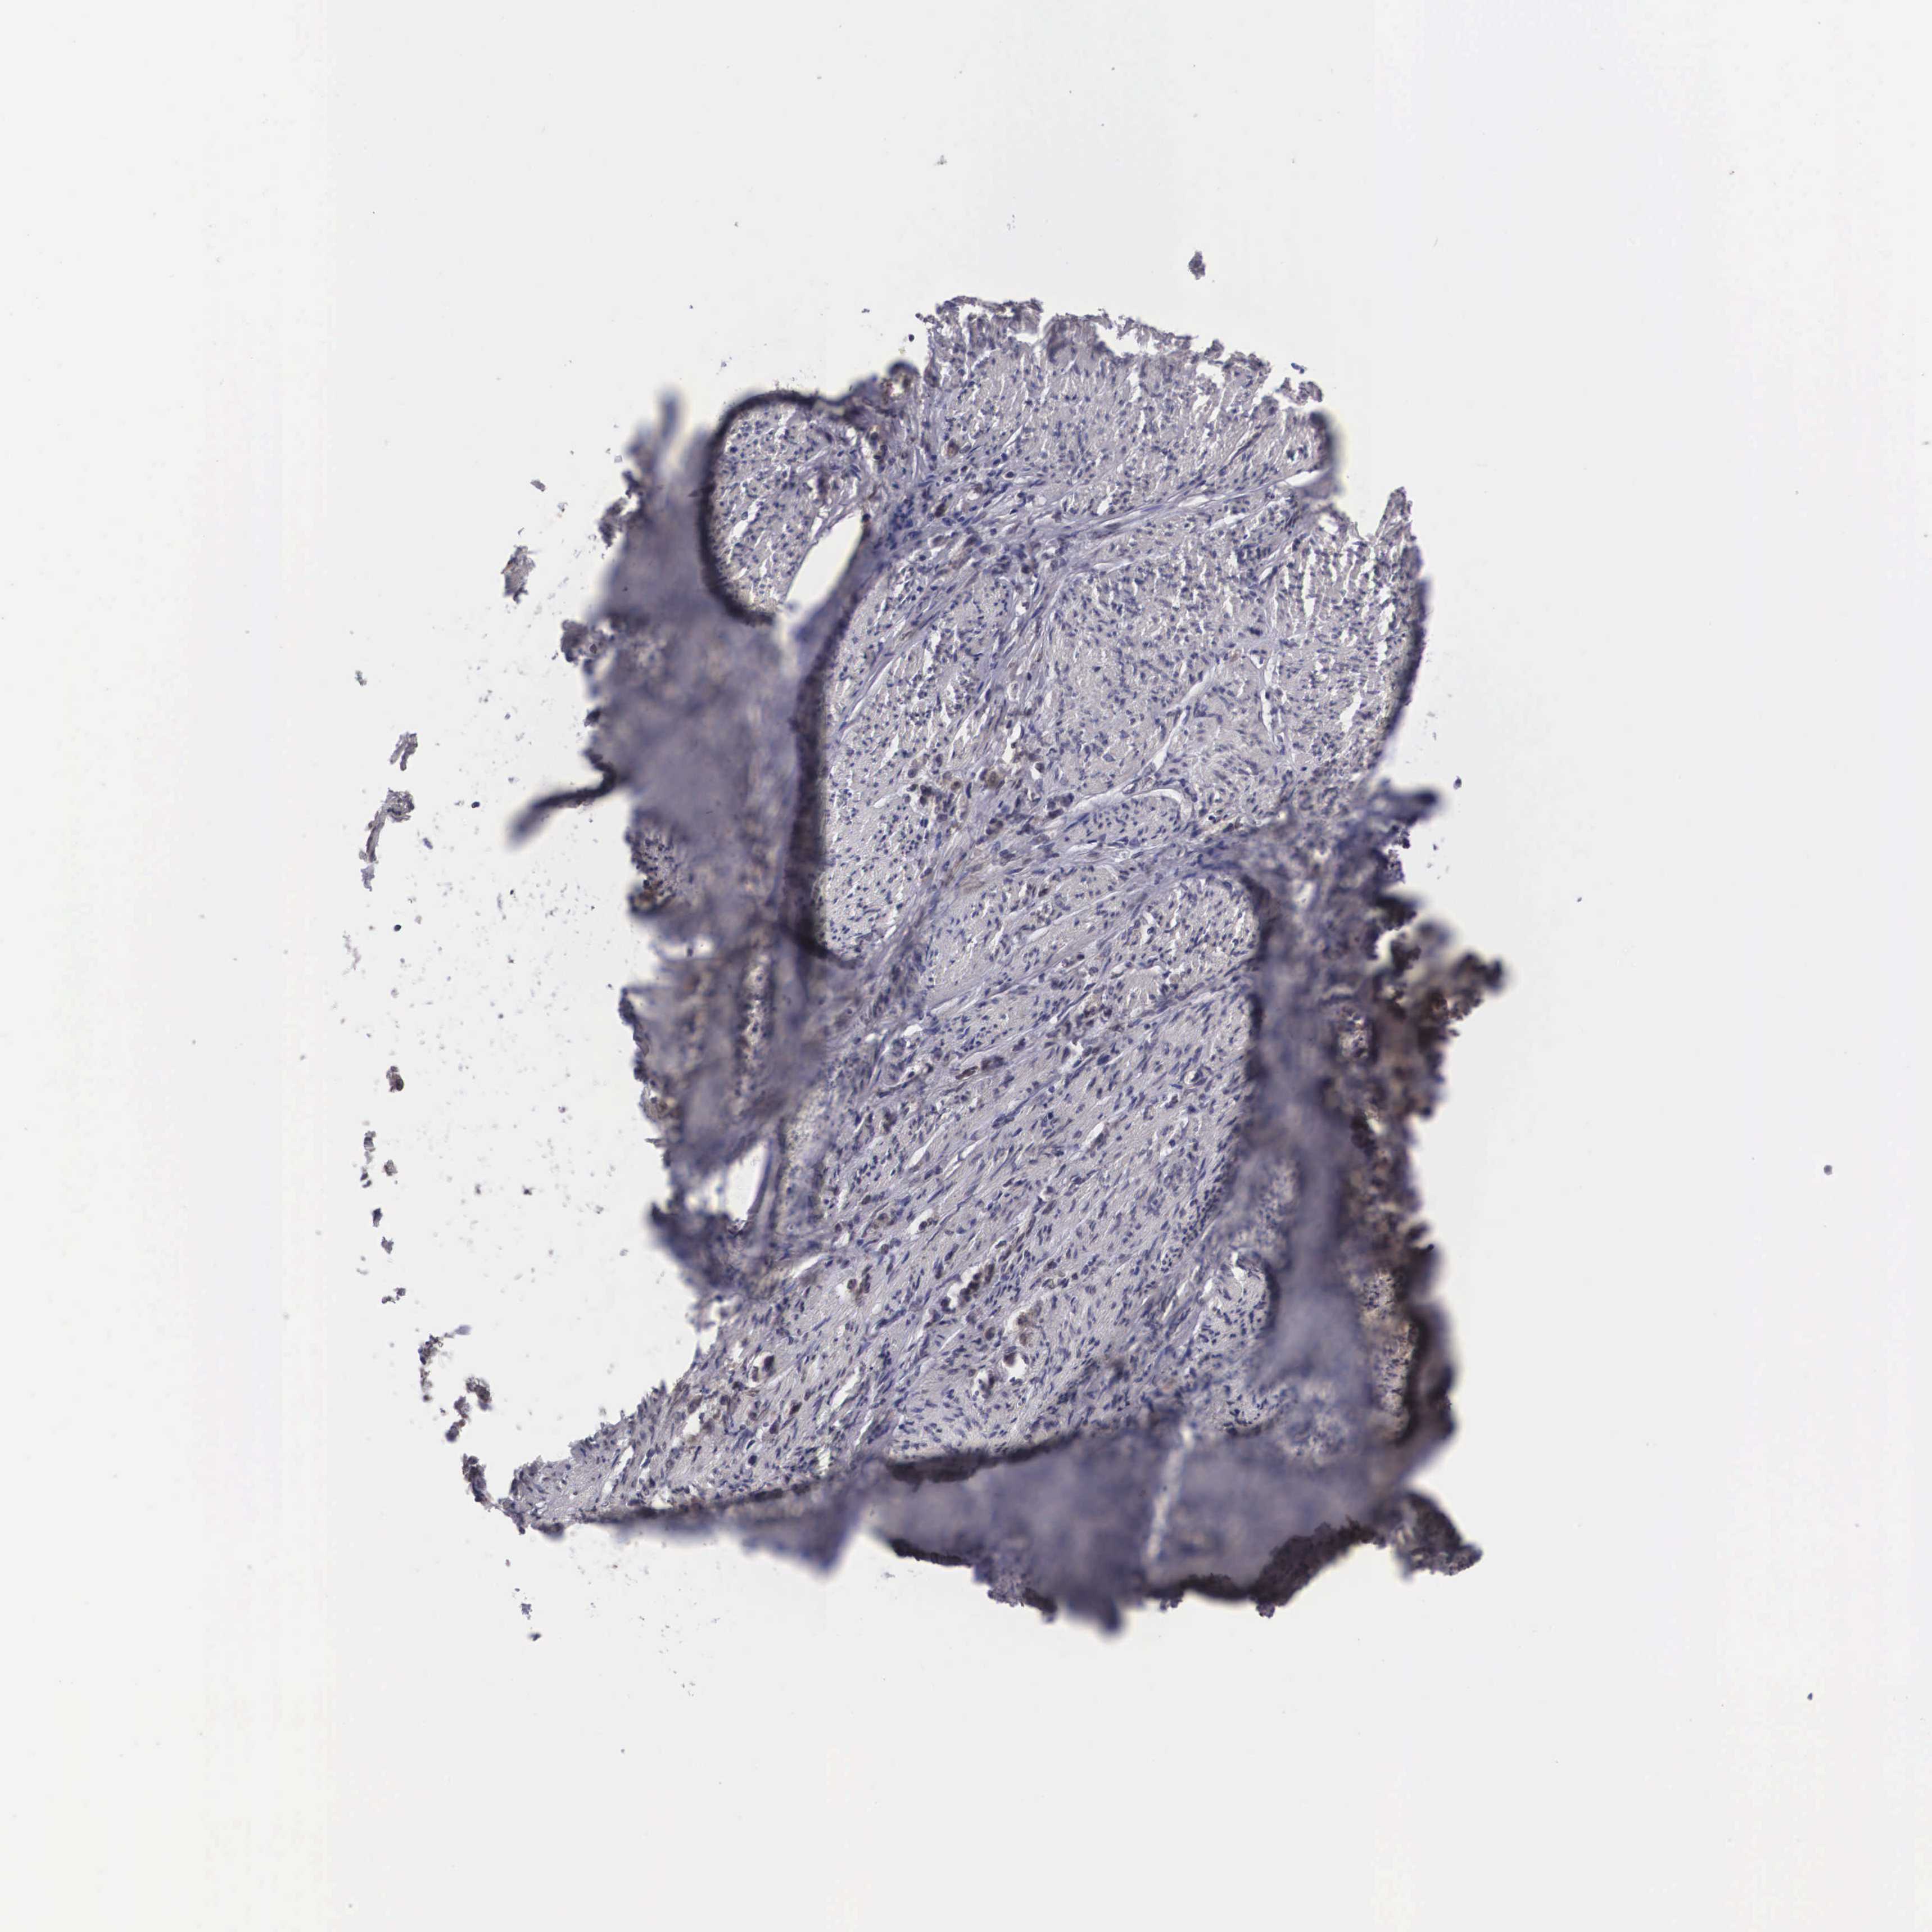

STOMACH CANCER - Protein expressioni

A mouse-over function shows sample information and annotation data. Click on an image to view it in a full screen mode. Samples can be filtered based on level of antibody staining by selecting one or several of the following categories: high, medium, low and not detected. The assay and annotation is described here.

Note that samples used for immunohistochemistry by the Human Protein Atlas do not correspond to samples in the TCGA dataset.

Antibody stainingi

Antibody staining in the annotated cell types in the current human tissue is reported as not detected, low, medium, or high, based on conventional immunohistochemistry profiling in selected tissues. This score is based on the combination of the staining intensity and fraction of stained cells.

Each image is clickable and will lead to virtual microscopy that enables deeper exploration of all samples and also displays staining intensity scores, fraction scores and subcellular localization as well as patient and tissue information for each sample.

Antibody HPA000633

Adenocarcinoma, NOS